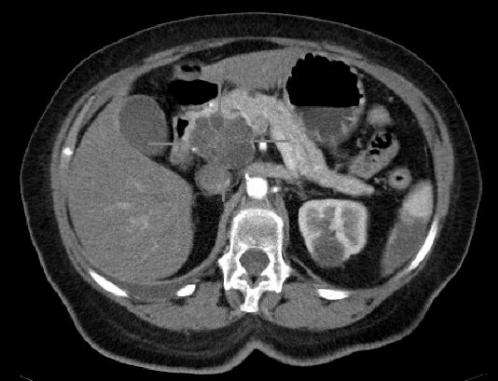

在本研究中,手术中取患者肿瘤样本,并移植到小鼠中以生长成新的胰腺肿瘤。

科学家们首先观察到,与正常胰腺相比,肿瘤中 MIR506 的水平较低。接下来,他们用 MIR506 处理实验性肿瘤细胞,以确定它是否以与卵巢癌和其他癌症相同的方式表现。他们发现用 MIR506 处理胰腺癌细胞抑制了恶性细胞生长以及导致癌症转移的细胞过程。